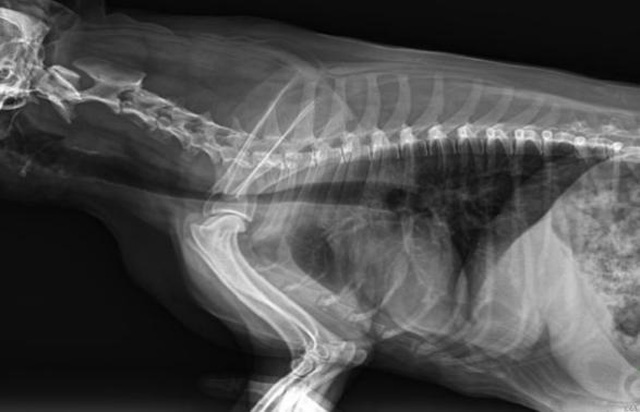

從臨床角度出發(fā),大力發(fā)展動(dòng)態(tài)DR,以精準(zhǔn)的診斷為小動(dòng)物保駕護(hù)航。寵物DR升級使用雙焦點(diǎn)球管,大尺寸平板探測器,超高頻逆變高壓發(fā)生器。醫(yī)用纖維板臺(tái)面,防止寵物劃傷。寵物DR整機(jī)小巧實(shí)用,骨略結(jié)構(gòu)和器官位置,分類詳細(xì),運(yùn)算更快,讓拍攝條件更科學(xué),有助于提高診斷的準(zhǔn)確性和效率。安裝移動(dòng)非常方便。低輸入電流設(shè)計(jì),220伏常規(guī)電壓。多品種動(dòng)物程序設(shè)定,滿足各個(gè)臨床需求。成像效果顯著,寵物不能言語表達(dá),導(dǎo)致誤診率居高不下。寵物診療均以經(jīng)驗(yàn)診斷為主的方式,確保最小化輻射降低對醫(yī)生及動(dòng)物的影響。以滿足精細(xì)化的寵物醫(yī)療需求,成為診斷寵物內(nèi)外科疾病的必備工具。使醫(yī)院更有競爭力,為醫(yī)院創(chuàng)收增光添彩。

寵物DR的操作流程是什么呢?第一步首先插上整機(jī)電源,然后按下主機(jī)電源。打開高壓發(fā)生器的電源,工作站主機(jī)電源。等待主機(jī)軟件的自動(dòng)啟動(dòng)。通過軟件登記檢查的寵物信息,選擇寵物檢查拍攝部位。調(diào)節(jié)限速器拍攝區(qū)域。關(guān)閉鉛房門,點(diǎn)擊開始拍攝按鈕。拍攝完成調(diào)整圖像并且輸出。